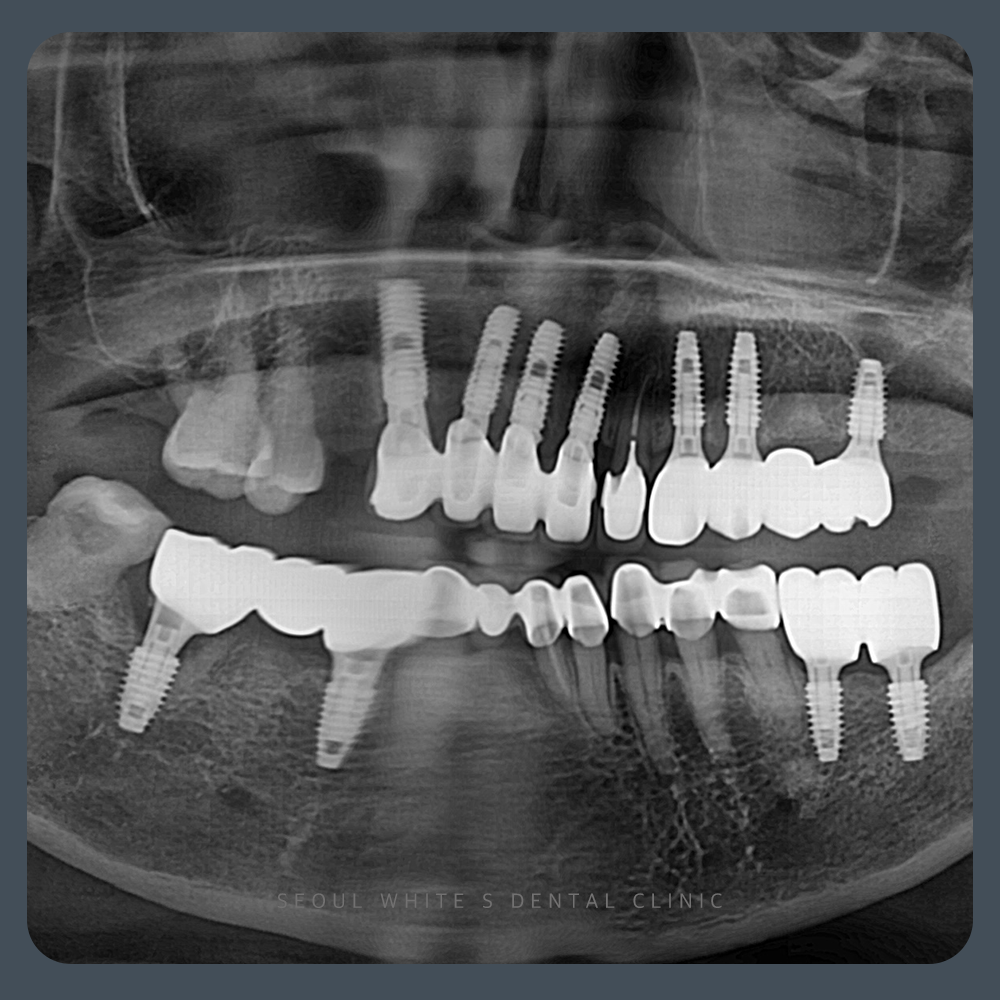

술 후

2024.11.27

수술을 진행하면서 확인한 결과, 상악 전치부의 근관 치료가 된 치아는 상태가 좋았기 때문에 보존하기로 결정하였고, 후방 부위에는 임플란트를 식립하였습니다. 하악 부위에서는 예후가 좋지 않은 치아들을 모두 제거한 후, 즉시 임플란트를 식립하여 내원 간격과 불편함을 줄였습니다. 일부 부위에는 골 이식이 필요했으며, 해당 부위에는 적절한 골 이식을 시행하여 치료했습니다. 전체적으로 수술 전 상태에 비해 골 높이가 안정적으로 확보되었고, 치료가 순조롭게 진행되었습니다.